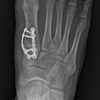

The bunion deformity, technically termed hallux abductovalgus or HAV, is a 3-plane positional deformity of the great toe and first metatarsal and can ultimately lead to pain with shoe wearing and walking. Conservative treatment is always favored first; however, the only way to truly eliminate the deformity itself is by surgical correction.

By Paul J. Betschart, ...